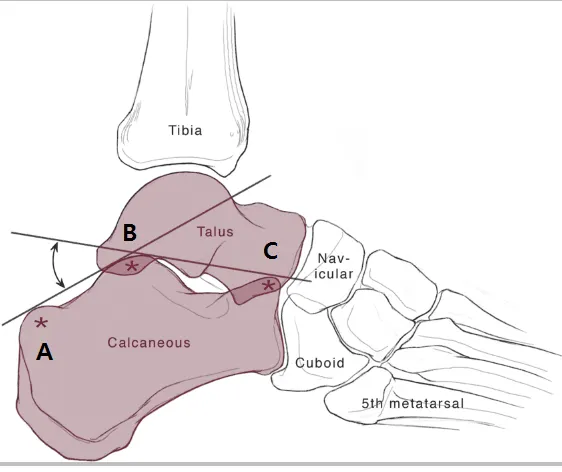

The Boehler angle

Post. articular surface의 highest point(B)와 Ant. process의 highest point(C)를 잇는 선

Post. articular surface의 highest point(B)와 Calcaneal tuberosity의 most sup. part(A)를

→ ⓧ과 ⓨ가 만나는 각도가 25~40°가 정상. 이 각이 25° 이하면 골절을 의심해야 한다.